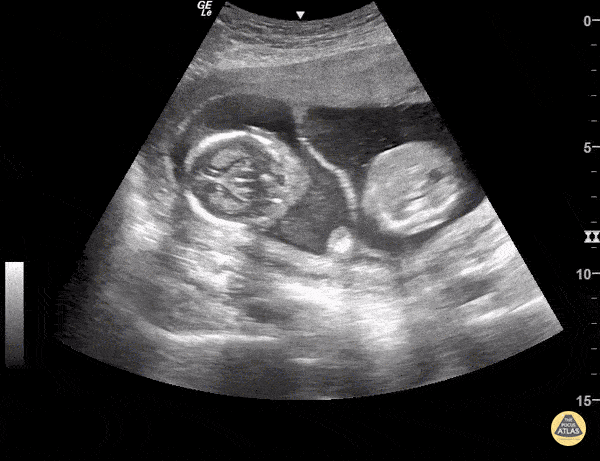

This is a normal transabdominal POCUS of twins separated by a membrane. Sukh Singh, MD